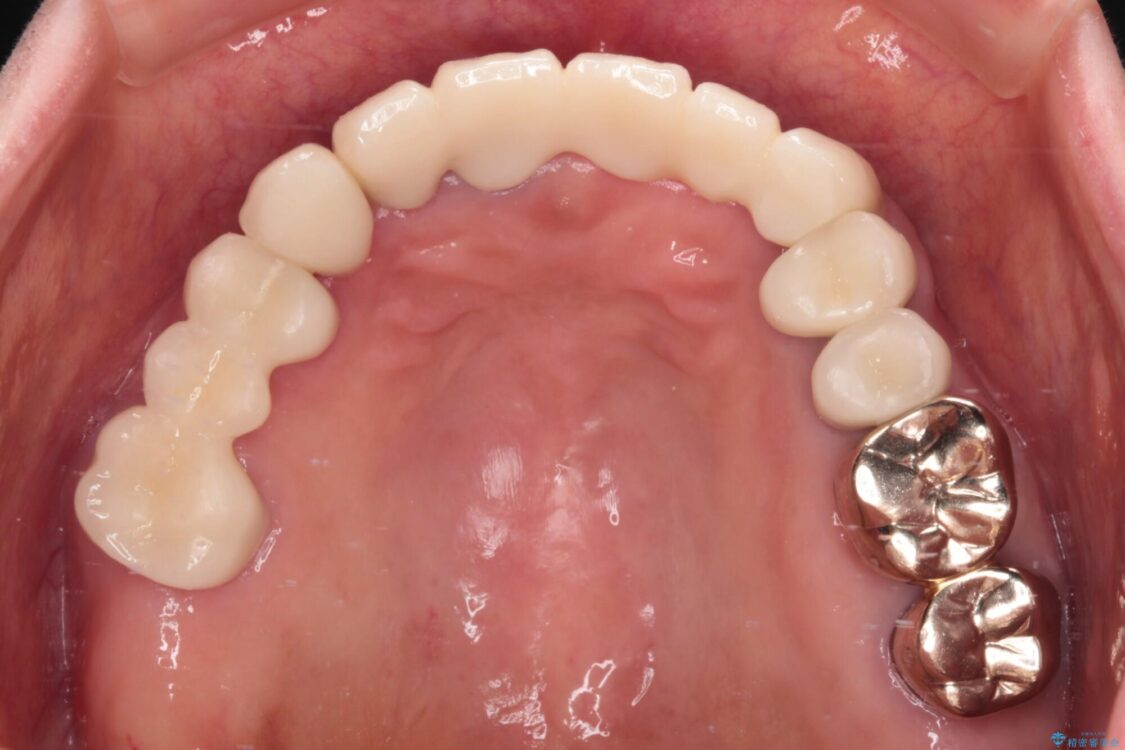

治療後

• 前歯をきれいにしたい インプラントや部分矯正を用いた総合歯科治療 治療後画像